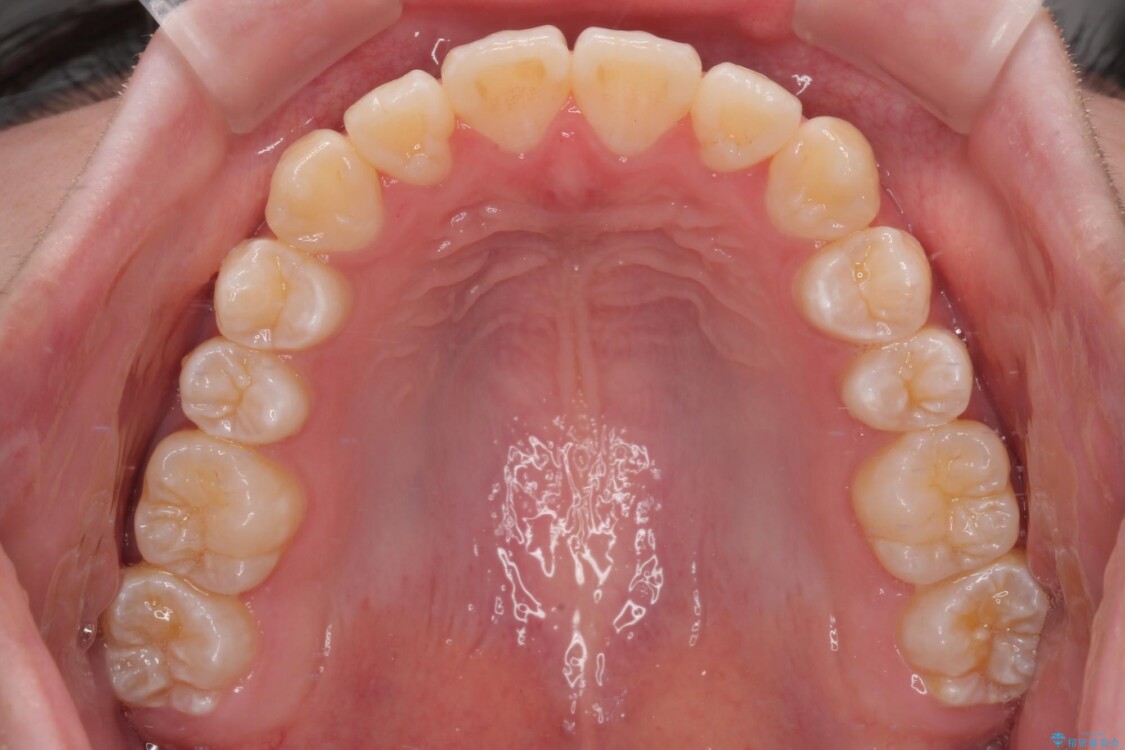

「前歯のデコボコ(叢生)をきれいに整えたい」とのことでご来院されました。

治療前

• 【モニター】前歯のデコボコをスッキリ解消!目立ちにくいワイヤー矯正でスピーディに治療完了 治療前画像